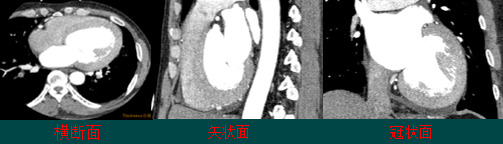

1、多平面重建(Multi-Planar Reformation, MPR)

MPR是把横断面的像素叠加起来回到三维容积排列上,根据需要组成的不同方位,重新组合新的断层图像。

较好地显示组织器官内复杂解剖关系,弥补横断图像观察的不足,有利于病变的准确定位。

2、曲面重建(CPR)

CPR与MPR类似,不同点是叠加成三维容积排列后,重新选取截面时按曲线走行。

优点:帮助医生在短时间内观察和研究血管组织。

缺点:重建路径的偏差对较小病灶容易遗漏或造成假性狭窄。

3、表面遮盖(SSD)

SSD是提取组织结构边缘的体素信息,把容积数据转换为一系列多边形表面片拟合的等值面,然后根据光照、明暗模型进行消隐和渲染。

用途:胸腹大血管、肺门及肺内血管、肠系膜血管、肾血管及骨与关节的三维显示。

缺点:容易造成虚假显示或显示面上产生空洞,且无法显示数据体内部的细节信息。

4、最大密度投影(MIP)

MIP是沿着虚拟的操作者视线方向,将相对密度最高的体素值投射到屏幕上,而形成的新的投影平面。

优势:较真实的反映组织的密度差异,主要用于显示具有相对较高密度的组织结构。

用途:观察血管的狭窄、扩张、充盈和缺损,可发现血管钙化,显示骨折情况,反映骨密度变化,清晰显示对内固定装置。